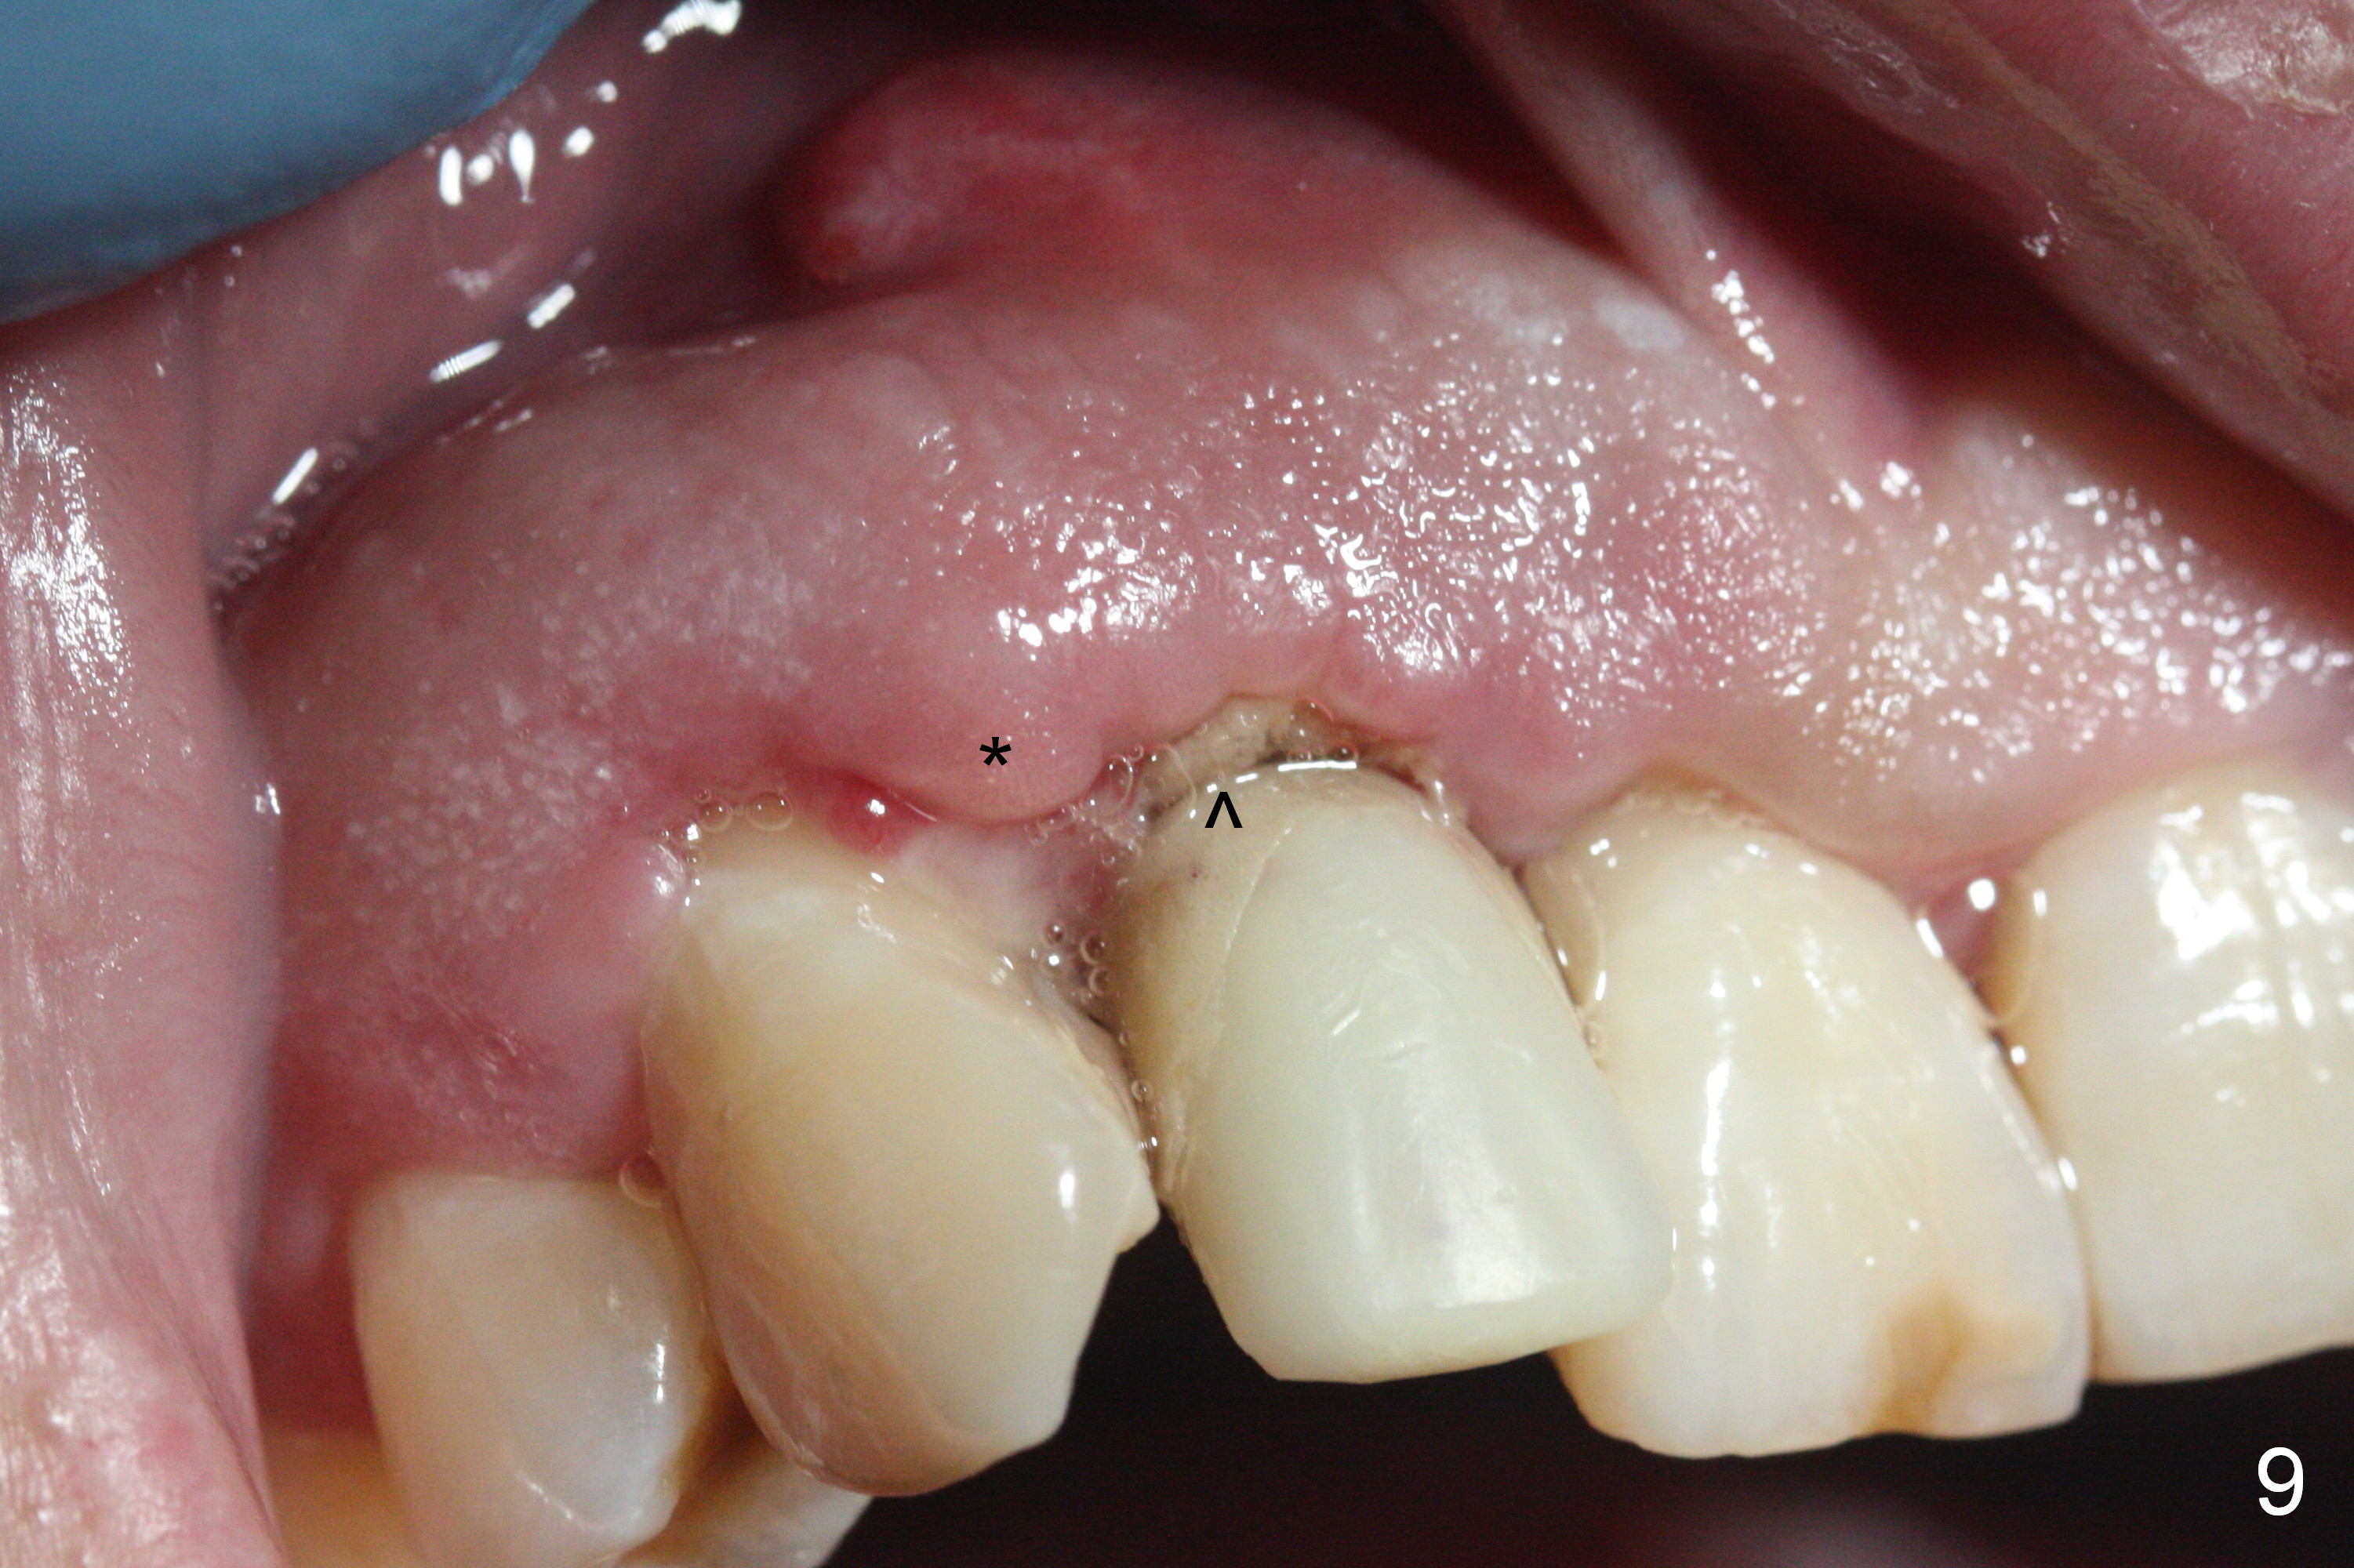

Sixteen days postop, the patient is doing fine, although the labial fistula has not disappeared (Fig.8 <). The detached distolabial papilla is healing (Fig.9 *) with mild bone graft exposure (^). The lacerated distopalatal papilla is also healing (Fig.10 *). These complications are related to flap surgery. The apical portion of the socket appears to have reduced 4 months postop (Fig.14). When the definitive restoration is delivered 5 months postop, there is gingival recession, including the distal of #8 (Fig.11 arrows, which is expected to improve over time) due to flap surgery. The labial plate collapse is minimal (Fig.12 *), while the palatal laceration (Fig.10) has healed (Fig.13). When the patient returns 1.5 years post cementation, there is increased bone density next to the coronal portion of the implant, equivalent to the bone graft (Fig.15 *). The fistula is absent (Fig.16). The crestal bone loss remains 2.5 years post cementation (Fig.17 *), although there is no sign of periimplantitis (magnification). Oral hygiene is poor. There is no change in the soft (gingival recession; data not shown) or hard tissues 3 years 8 months post cementation (Fig.18).